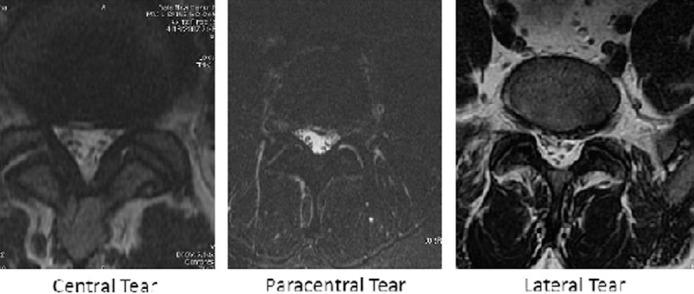

Patients undergoing a single-level anterior disc replacement from L3-S1 at a single site by a single surgeon were evaluated preoperatively for the presence or absence of annular tears with magnetic resonance imaging. All patients were part of either the ProDisc (n = 41) (Synthes, Paoli, Pennsylvania) or Activ-L (n = 19) (Aesculap [B. Braun Melsungen AG], Tuttlingen, Germany) lumbar prospective clinical trials. In those patients with annular tears, the location of the tear (central, paracentral, or lateral) was documented. Patients were assessed at 6 and 12 months after lumbar total disc arthroplasty with the Oswestry Disability Index (ODI), visual analog scale (VAS) score for back pain, VAS score for leg pain, and radiographic imaging. All radiographic evaluations were conducted by an attending neuroradiologist and an attending spinal surgeon, and reliability testing was performed. An analysis of variance was performed among the 3 anatomic locations of annular tears.

A total of 60 patients were included and had complete 12-month follow-up. The prevalence of annular tears among all patients was 42% (n = 25). Outcome data in patients without annular tears were as follows: ODI, 66% preoperatively and 26% postoperatively; VAS score for back pain, 8.0 preoperatively and 2.6 postoperatively; and VAS score for leg pain, 2.9 preoperatively and 1.2 postoperatively. Among those patients with tears, the prevalence of central tears was 80%, the prevalence of paracentral tears was 12%, and the prevalence of lateral tears was 8%. Outcome data in patients with central tears were as follows: ODI, 66% preoperatively and 26% postoperatively; VAS score for back pain, 7.8 preoperatively and 2.6 postoperatively; and VAS score for leg pain, 5.2 preoperatively and 0.5 postoperatively. Outcome data in patients with paracentral tears were as follows: ODI, 86% preoperatively and 59% postoperatively; VAS score for back pain, 8.8 preoperatively and 3.3 postoperatively; and VAS score for leg pain, 5.0 preoperatively and 5.4 postoperatively. Outcome data in patients with lateral tears were as follows: ODI, 6.5 preoperatively and 2.6 postoperatively; VAS score for back pain, 9.2 preoperatively and 0.2 postoperatively; and VAS score for leg pain, 1.4 preoperatively and 0.7 postoperatively. In those patients with paracentral tears, there was a significantly higher incidence of postoperative radicular symptoms both from an intensity standpoint and from a duration standpoint. Other complications did not vary among those patients with or without annular tears.

Although patients with annular tears and patients without annular tears improve after lumbar artificial disc replacement, those with central annular tears or without tears have significantly lower disability scores than those with paracentral tears or lateral tears, whose outcome scores showed significantly less improvement (P ≤ .03). In particular, patients with central tears have less postoperative leg pain than those with paracentral annular tears. In this study the presence or absence of an annular tear on magnetic resonance imaging was not a significant predictive factor for clinical outcome. Further investigation regarding the effects of paracentral annular tears and surgical techniques should be explored.